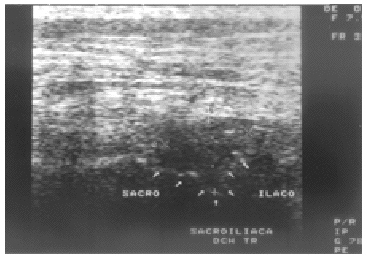

Durante su estancia hospitalaria, dado el mal estado general de la paciente y sus antecedentes, tras la extracción de hemocultivos y ante la sospecha de sacroileítis infecciosa se decidió iniciar tratamiento intravenoso empírico con cloxacilina y tobramicina. Dada la mala evolución de la enferma se consideró necesario intentar obtener muestras de la articulación sacroilíaca para su posterior cultivo, para ello se realizó una ecografía de las articulaciones sacroilíacas con sonda lineal de 7,5 MHz en la que se visualizó perfectamente la interlínea articular así como la existencia de derrame articular en forma de abombamiento hipoecoico, con ecos internos, de la cápsula de la articulación sacroilíaca derecha, sin alteración de los márgenes corticales de sacro e ilíaco (fig. 1). Ante la evidencia de derrame articular se realizó punción-aspiración guiada por ecografía y se extrajeron 3 ml de líquido purulento, en dos tomas diferentes, que se enviaron a cultivo.

Figura 1. Corte ecográfico de la articulación sacroilíaca derecha. Nótese el abombamiento hipoecoico de la cápsula articular de la articulación sacroilíaca de 16 *19 mm, compatible con derrame en dicha articulación. Las flechas indican los rebordes corticales de sacro e ilíaco. Sobre el área hipoecoica se dirigió la aguja de aspiración.